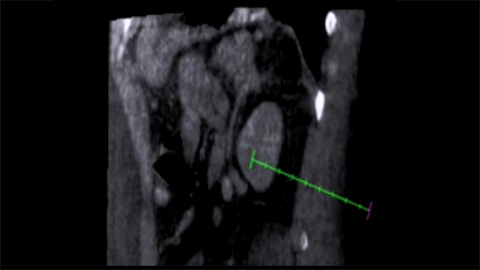

XperGuide Ablation provides comprehensive assistance for treatment planning and live needle guidance. It offers unique Parallax Correction to plan needle trajectories for off-center lesions [9].

XperGuide Ablation displays the virtual needle path to assist in multiple needle planning. It shows needle characteristics such as ablation zone/isotherm to confirm complete tumor coverage prior to ablation.

XperGuide provides highly accurate live image guidance of each needle to a targeted position by overlaying pre-planned trajectories with fluoroscopic imaging [10].

With CBCT acquire a post-ablation CBCT to demonstrate the extent of tumor coverage and confirm completeness of your treatment.